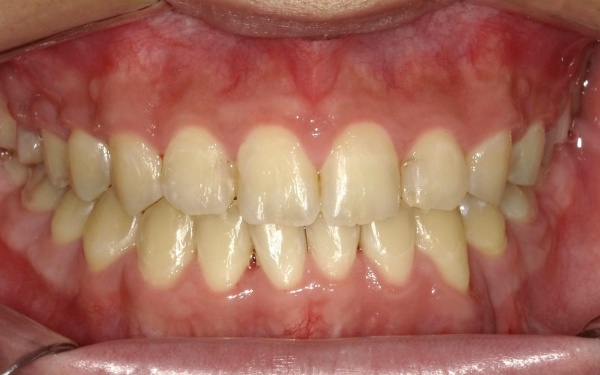

治療後

治療後画像

最後に、審美性、噛み合わせ、機能性などに問題がないことを確認し、治療を終了しました。

治療後画像 治療後画像 治療後画像 治療後画像 治療後画像 治療後画像